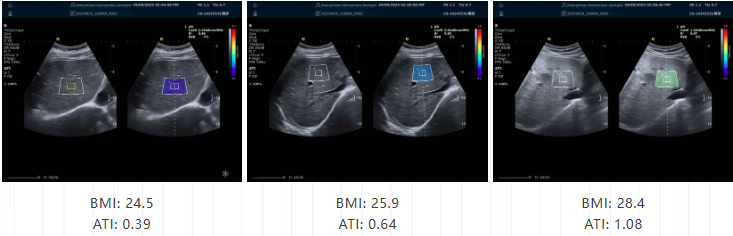

如下图ePascal东风系列采用 ATITM 技术测量肝脏声衰减程度的图像,二维彩色衰减图中蓝色区域代表衰减系数低,属正常情况。图像右上角有相对应测量数据。

·Coeff:平均衰减系数(标准单位dB/cm/MHz)

·R2:质控参数(0-1),≥0.9可信

·RSD:相对标准偏差(%),<10%均匀性高,≥10%均匀性低。

脂肪肝程度定量监测

中国成年人:体重过低:BMI<18.5,正常范围:18.5≤BMI≤23.9,超重:24≤BMI≤27.9,肥胖:BMI>28